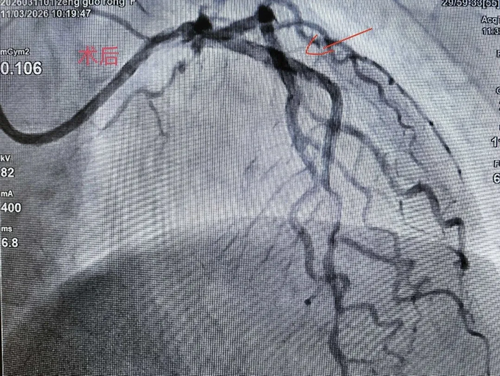

术中,团队先后3次使用1.5万转/分的旋磨头,精准击碎钙化"硬壳"。旋磨成功后,顺利行球囊扩张并于前降支植入支架。同期,团队还对右冠病变进行了介入处理。术后患者血管开通效果理想,目前正在康复中。